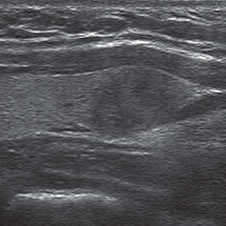

Figura 14. a) Cáncer papilar

hipoecogénico de

bordes irregulares y lobulados,

no encapsulado,

hipovascular, que muestra

un grupo de micro y

macrocalcificaciones centrales

(flecha abierta) con

sombra acústica; b) Nódulo

coloideo avascular

(flecha) marcadamente hipoecogenico.